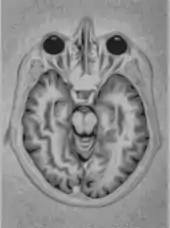

Magnetic resonance imaging

A magnetic resonance imaging instrument (MRI scanner), or "nuclear magnetic resonance (NMR) imaging" scanner as it was originally known, uses powerful magnets to polarize and excite hydrogen nuclei (i.e., single protons) of water molecules in human tissue, producing a detectable signal which is spatially encoded, resulting in images of the body.[5] The MRI machine emits a radio frequency (RF) pulse at the resonant frequency of the hydrogen atoms on water molecules. Radio frequency antennas ("RF coils") send the pulse to the area of the body to be examined. The RF pulse is absorbed by protons, causing their direction with respect to the primary magnetic field to change. When the RF pulse is turned off, the protons "relax" back to alignment with the primary magnet and emit radio-waves in the process. This radio-frequency emission from the hydrogen-atoms on water is what is detected and reconstructed into an image. The resonant frequency of a spinning magnetic dipole (of which protons are one example) is called the Larmor frequency and is determined by the strength of the main magnetic field and the chemical environment of the nuclei of interest. MRI uses three electromagnetic fields: a very strong (typically 1.5 to 3 teslas) static magnetic field to polarize the hydrogen nuclei, called the primary field; gradient fields that can be modified to vary in space and time (on the order of 1 kHz) for spatial encoding, often simply called gradients; and a spatially homogeneous radio-frequency (RF) field for manipulation of the hydrogen nuclei to produce measurable signals, collected through an RF antenna.

Like CT, MRI traditionally creates a two-dimensional image of a thin "slice" of the body and is therefore considered a tomographic imaging technique. Modern MRI instruments are capable of producing images in the form of 3D blocks, which may be considered a generalization of the single-slice, tomographic, concept. Unlike CT, MRI does not involve the use of ionizing radiation and is therefore not associated with the same health hazards. For example, because MRI has only been in use since the early 1980s, there are no known long-term effects of exposure to strong static fields (this is the subject of some debate; see 'Safety' in MRI) and therefore there is no limit to the number of scans to which an individual can be subjected, in contrast with X-ray and CT. However, there are well-identified health risks associated with tissue heating from exposure to the RF field and the presence of implanted devices in the body, such as pacemakers. These risks are strictly controlled as part of the design of the instrument and the scanning protocols used.

Because CT and MRI are sensitive to different tissue properties, the appearances of the images obtained with the two techniques differ markedly. In CT, X-rays must be blocked by some form of dense tissue to create an image, so the image quality when looking at soft tissues will be poor. In MRI, while any nucleus with a net nuclear spin can be used, the proton of the hydrogen atom remains the most widely used, especially in the clinical setting, because it is so ubiquitous and returns a large signal. This nucleus, present in water molecules, allows the excellent soft-tissue contrast achievable with MRI.